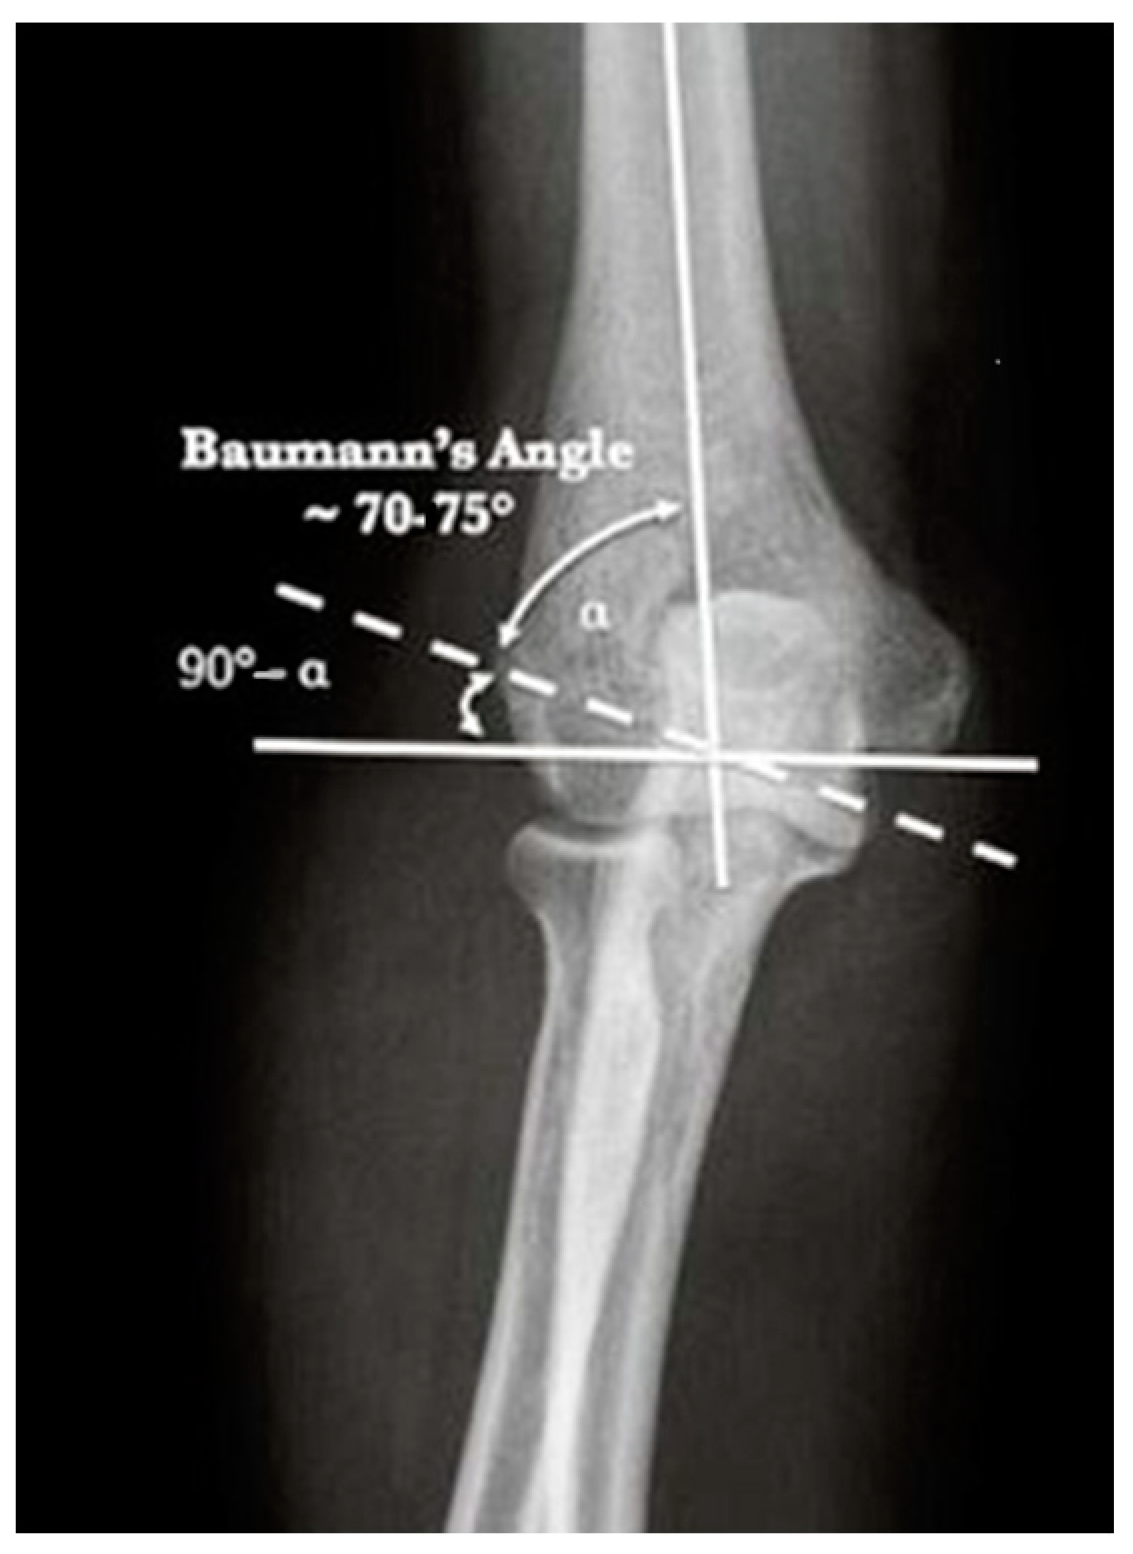

| Carrying Angle | 12.3° | 4.28 | 5–22° |

| Contralateral Carrying Angle | 12.3° | 3.87 | 5.9–20° |

| Baumann Angle | 78.9° | 13.5 | 60.4–112° |

| Contralateral Baumann Angle | 79.1° | 12.7 | 63–118.8° |